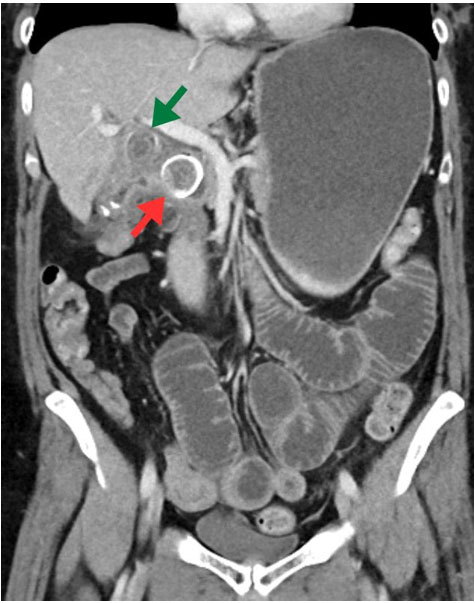

Case Report: A 54-year-old woman presented with right lower abdominal pain and fever for five days. Fourteen years earlier, a computed tomography (CT) scan revealed a cystic lesion in the appendix; however, no treatment was initiated. On admission, her temperature was 38.5 °C, with mild tenderness. Blood tests showed elevated C-reactive protein (CRP) levels, and CT imaging revealed a 9 cm inflamed cystic lesion. Antibiotics were ineffective, and the patient underwent an ileal resection. Laparotomic resection was selected due to the patient’s prior history of surgery, suspected adhesions secondary to inflammation, and the considerable tumor size. The tumor was removed intact. Histopathological analysis confirmed a LAMN with associated infection. The postoperative ileus was treated with decompression, and the patient was discharged on day 20.